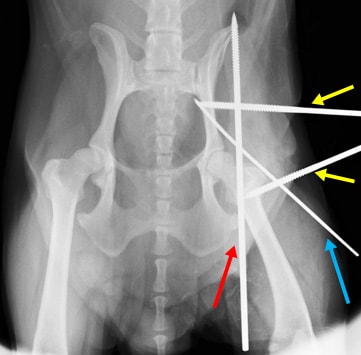

股関節脱臼① 関節包再建術とDeVitaピン法と伸縮性創外固定装置を併用して整復した一例

関節包再建術後、大腿骨頭の背側脱臼を防ぐためのDeVitaピンを挿入します。(赤矢印)

|

DeVitaピン(赤矢印)とクロスピン(青矢印)を挿入後、大腿骨の外旋を防ぎ、